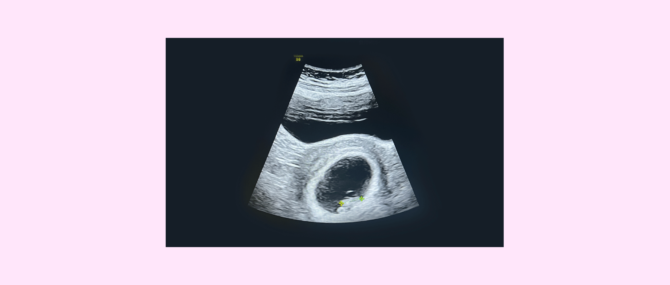

First ultrasound scan

Broadly speaking, performing an ultrasound scan before the eighth week of pregnancy is unadvisable. The rational for this is that it is possible that the embryo cannot be seen yet because it is too early. This causes great stress on the woman as she may think that something is wrong.

According to experts, ideally the first ultrasound scan should be performed on week 8 or later. At this point, it allows us to measure the embryo for the first time in order to monitor fetal development. Confirming the heartbeat helps to confirm that it is an ongoing pregnancy.

When pregnancy has been achieved via Assisted Reproduction, the first ultrasound scan is typically performed earlier than in natural pregnancies, usually on week 7 of pregnancy after a positive beta-hCG test. The goal of this action is to see the number of gestational sacs to determine whether it is a multiple pregnancy, and if everything is going as it should.